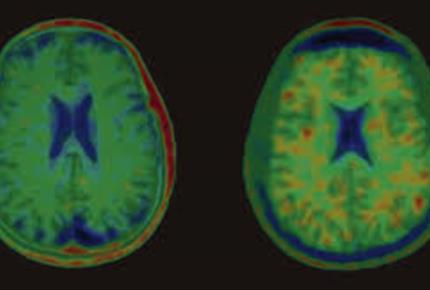

قطرات فراموش شده-مجله مادر و کودک گوپی

عاقبت سهل انگاری در مدیریت بیماران مبتلا به خونریزی داخل مغزی